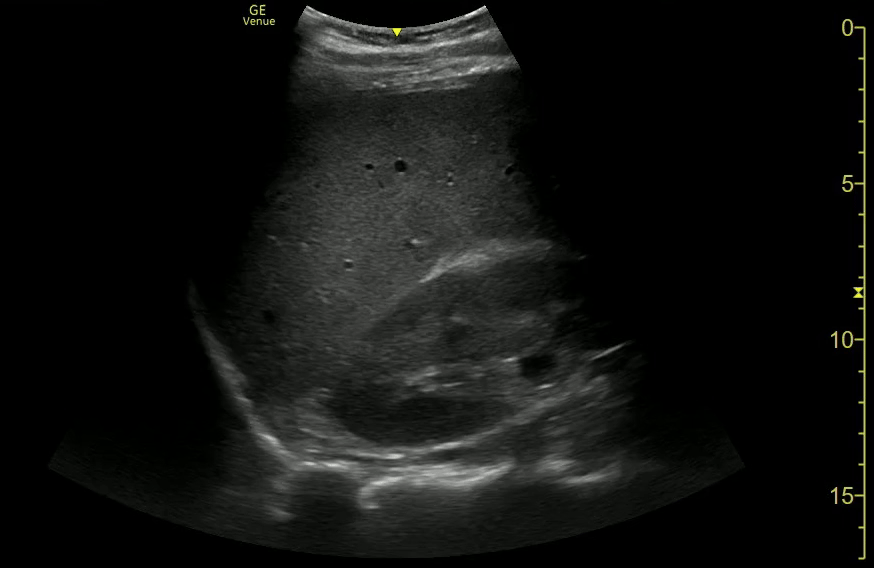

Hepatorenal Free Fluid (Morisons Pouch)

Caudal Liver Free Fluid

Splenic Laceration